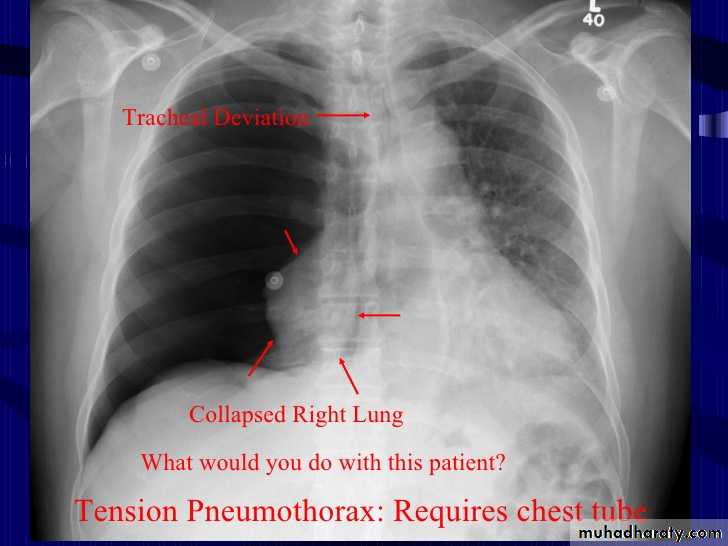

The mediastinum is pushed to the opposite side

Tension pneumothorax

Radiolucent area devoid of lung markings in the area of the left lung with visible viseral pleural edge.Tension Pneumothorax

Radiolucent area devoid of lung markings in the area of the right lung with visible viseral pleural edge. The mediastinum is pushed to the opposite side